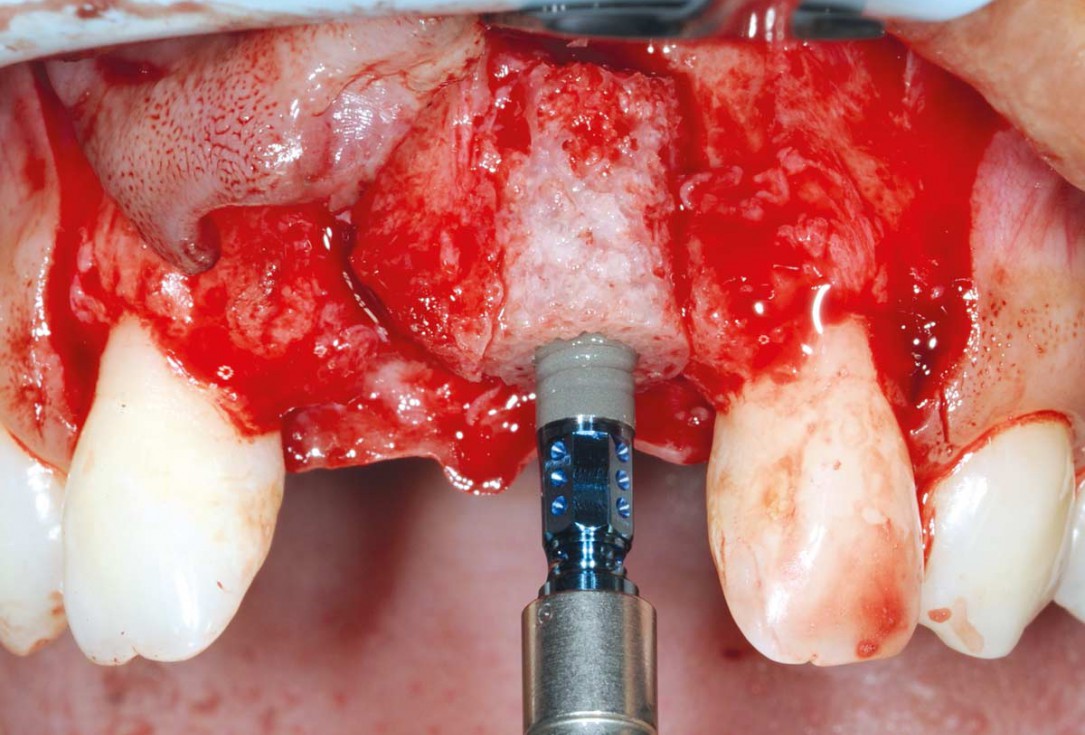

3/26 - Big bone defect visible after opening the flapBone augmentation in aesthetic zone with maxgraft® bonering - Dr. A. Patel